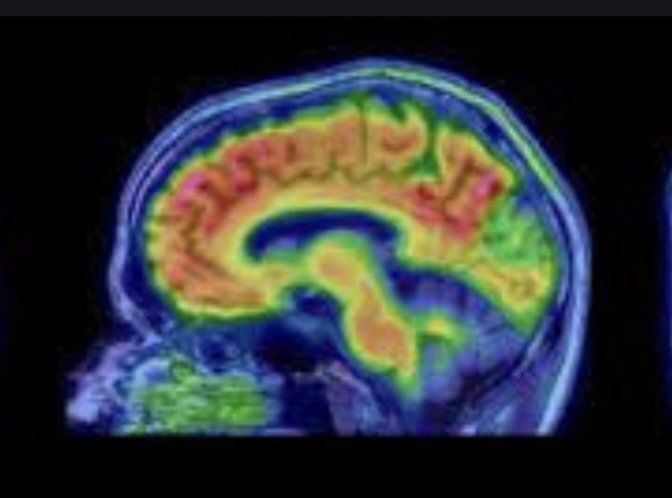

Bei Dystonie liegt, vereinfacht gesprochen, ein Schaltstellen und/oder Schaltkreisproblem vor. So funktioniert bei Dystoniebetroffenen grundsätzlich die motorische Zentralschaltstelle in der Tiefe des Gehirns - ein Teil der Basalganglien - nicht normal (siehe den zentral blauen Bereich im Abbild).

Was genau defekt ist, entzieht sich allerdings noch der wissenschaftlichen Erkenntnis. Bekannt ist lediglich, dass aktivierende und hemmende Signale zwar "produziert", aber irgendwie nicht richtig aufeinander abgestimmt ausgesendet werden ...

Der Schaltstellendefekt führt sodann wiederum dazu, dass Schaltkreise im Gehirn, die für die Bewegung der Skelettmuskulatur verantwortlich sind (siehe Teile der roten und grünen Bereiche) nicht so funktionieren, wie sie eigentlich funktionieren sollten.

All dass führt schlussendlich dazu, dass die Muskeln bei Dystonie, was deren An- und Entspannung anbelangt, sozusagen ein Eigenleben führen, dem die Betroffenen schonungslos ausgesetzt sind und ohne Therapie - in welcher Form auch immer - kaum bis gar nicht Einhalt gebieten können.